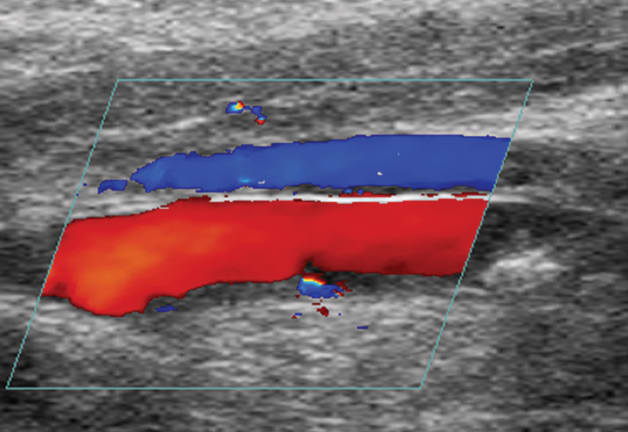

In the histotripsy system, an imaging transducer is closely aligned with the cloud-generating therapy transducer. This allows researchers to view microbubble cloud activity as it occurs. “We can see in real time when the cloud is generated, if it’s working, and if it has been effective in breaking up the clot,” says Xu. They also use color Doppler imaging to assess improvements in blood flow during the process.

Since April 2010, Xu's team has made progress in two areas of clinical translation of the histotripsy thrombolysis technique. First, an initial series of animal studies were conducted in a pig deep vein thrombosis (DVT) model, successfully demonstrating the feasibility and safety of histotripsy. These experiments revealed that blood clots in the femoral vein can be removed by histotripsy without damaging the overlying tissue. No clinically significant adverse effects were observed. Second, a compact ultrasound therapy transducer integrated with an ultrasound imaging probe has been designed and built specifically for the DVT application. The therapy transducer has successfully passed their initial lab testing.